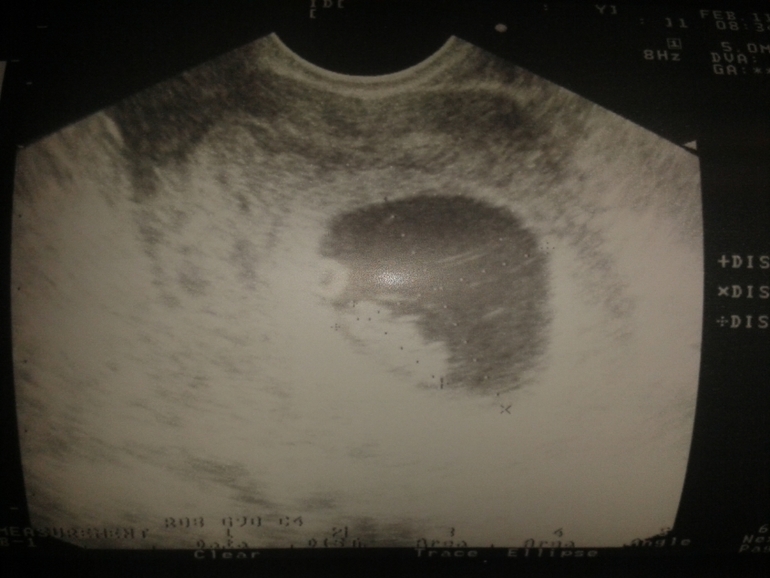

Ниже фота нашего УЗИ и заключения.

На консультации в ЖК, выбор женской консультации/гинекологаДевчат! Вчера-таки попала я наконец к своей Гине. Все у нас ОК! Матка на ощупь "приличная по размеру", по УЗИ эмбрион на месте, опережает развитие на 2 недельки (тянет на 8 нед по размерам, а у нас эмбр. срок 5,5 нед, акушерский 7,5 нед.). КТР 16мм. Сб+ (150 уд/мин). Довольная я - как слон ))). Правда вместе с маткой разрослась моя миомка с 1,2 до 1,8см. Но это не страшно, т.к. внутристеночная и растет наружу, поэтому малышу не будет мешать. Гиня говорит после родов сожмется до первоначальных размеров вместе с маткой. И плохая новость: я у них отношусь к высокой степени риска (гиперандрогения, миома, диабет =12 баллов), поэтому зав.отделением не стремится давать согласие, чтоб меня поставили у них в клинике на учет. Просит предоставить заключение от моего эндокринолога, что в период моей Б к инсулинотерапии прибегать не придется. Тогда возьмут меня "на консилиум" на право постановки на учет. Пойду теперь 25.02 к эндокринологу. Сдам заранее все возможные анализы. И буду ждать, что мне по судьбе написано. В принципе уже и не очень хочется мне туда на учет )). За вчерашний визит отдала 5600р. (конс, УЗИ, мазок срочный). Если так раз в 2-3 нед пойдет, то и разориться не долго. А на программу по вынашиванию меня не возьмут опять же из-за высокого риска (т.е. оплата по факту по базовым тарифам, все анализы и процедуры, посещение смежных спецов - только у них). Тогда уж лучше буду делать как в прошлую Б: для обменки и б/п анализов ходила в ЖК, а для контроля назначений и здоровья раз в мес к своей Гине. Вот такие у меня новости ))).